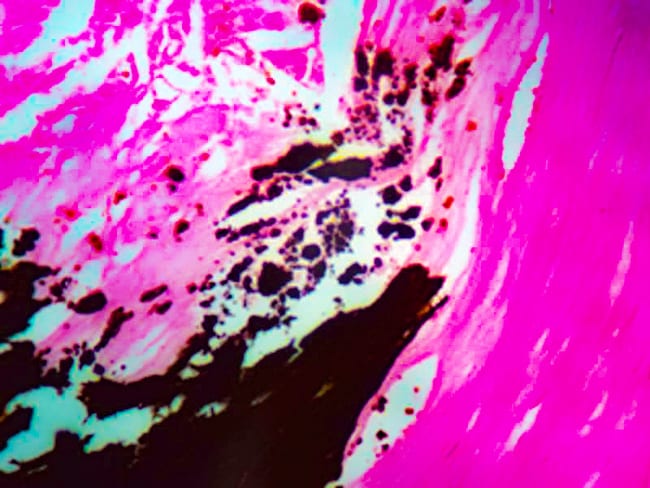

Diagnostic Biosystems VON KOSSA Von Kossa

The Calcium Stain Kit (Modified Von Kossa) is intended for use in the histological visualization of calcium deposits in paraffin sections.